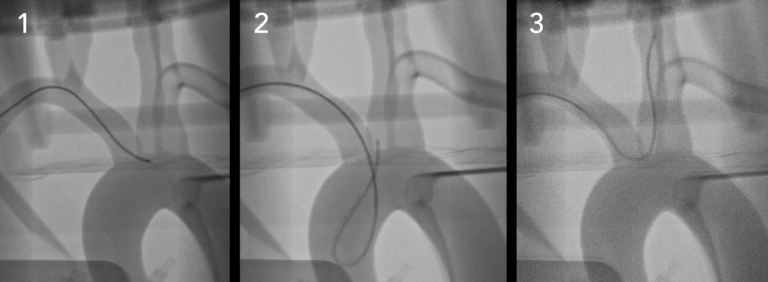

●具有清晰視野的多種成像模式– CT,熒光檢查和照相機(jī)

●執(zhí)行EVAR,TEVAR,F(xiàn)EVAR,TAVR等

重復(fù)模擬具有真正生理功能的血管內(nèi)病例。?生理和解剖學(xué)上準(zhǔn)確的人類硅膠血管?在模擬血管內(nèi)手術(shù)時,PRO?可提供的逼真的模擬體驗(yàn):